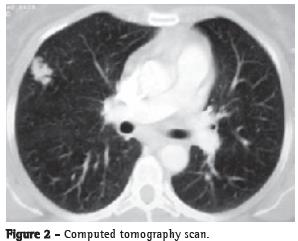

Computed tomography of the ch parts and lobulated borders, measuring 2.0 × 1.5 cm and located in the lateral segment of the middle lobe. There were no enlarged mediastinal lymph nodes (Figure 2).